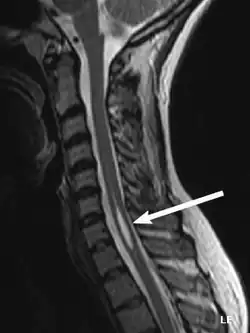

Physicians now use magnetic resonance imaging (MRI) to diagnose syringomyelia. The MRI radiographer takes images of body anatomy, such as the brain and spinal cord, in vivid detail. This test will show the syrinx in the spine or any other conditions, such as the presence of a tumor. MRI is safe, painless, and informative and has greatly improved the diagnosis of syringomyelia.[18]

The physician may order additional tests to help confirm the diagnosis. One of these is called electromyography (EMG), which show possible lower motor neuron damage.[19] Note this test isn't used diagnostically for injuries to the spine but to nerves and muscles. This would be part of a patient's rehab routine. In addition, computed axial tomography (CT) scans of a patient's head may reveal the presence of tumors and other abnormalities such as hydrocephalus.[20]

Like MRI and CT scans, another test, called a myelogram, uses radiographs and requires a contrast medium to be injected into the subarachnoid space. Since the introduction of MRI, this test is rarely necessary to diagnose syringomyelia.[21]

The possible causes are trauma, tumors, and congenital defects. It is most usually observed in the part of the spinal cord corresponding to the neck area. Symptoms are due to spinal cord damage and include pain, decreased sensation of touch, weakness, and loss of muscle tissue. The diagnosis is confirmed with a spinal CT, myelogram or MRI of the spinal cord. The cavity may be reduced by surgical decompression.[22]